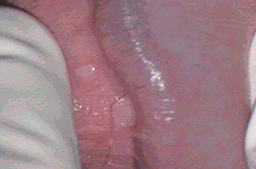

El resultado de una valoración colposcópica de paciente con lesión displásica siempre será confirmado por el estudio histopatológico que realiza el médico anatomopatólogo (estudio de la biopsia tomada en la colposcopía) . A continuación presentamos imágenes histológicas con sus diagnósticos.

• Lesiones planas por VPH en pene